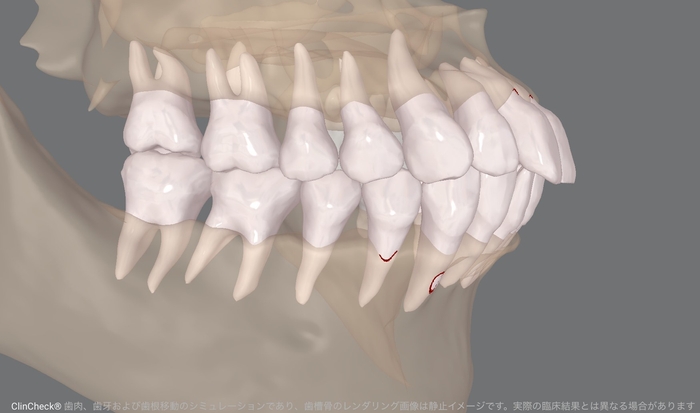

矯正前のデジタルスキャンデータにCT画像を組み合わせたイメージ